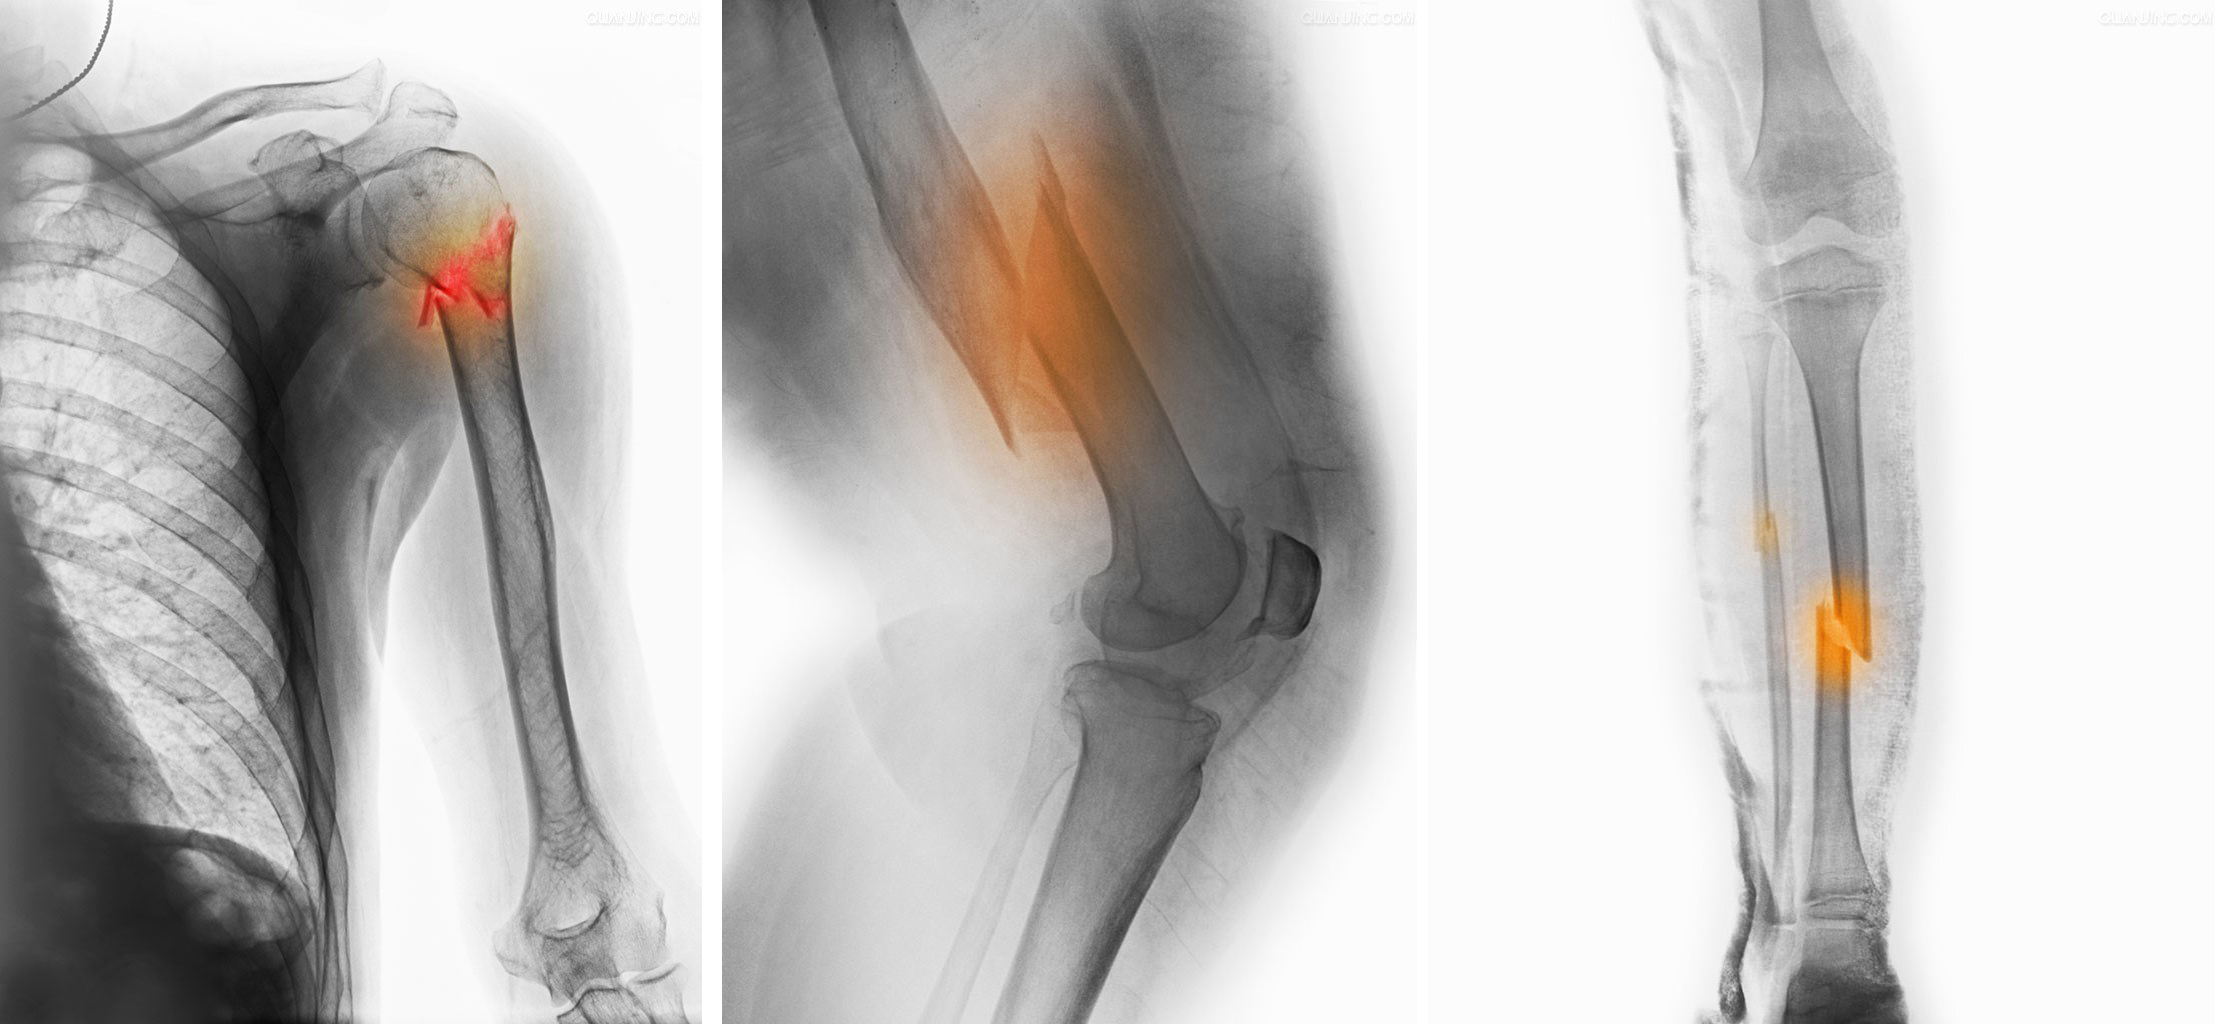

创伤骨科中心(创伤、手足外及外周神经)诊疗范围

1、各类四肢骨折脱位:特别对于关节周围骨折,通过微创和传统手术治疗,减少关节骨折致残、畸形、功能不良的后遗症。

2、老年骨质疏松骨折:对于高龄、内科合并症较多的骨质疏松骨折,发挥多学科合作的优势实施综合治疗。广泛应用微创的手段,治疗高龄老人常见的脊柱压缩骨折、髋部骨折、桡骨远端骨折、肱骨近端骨折等骨质疏松骨折。

3、擅长处理严重创伤:如肢体骨折复杂髋臼骨折;复杂骨盆骨折;骨折合并血管神经损伤;骨折合并软组织缺损伴骨外露;以及骨折不愈合、骨折畸形愈合矫正等。